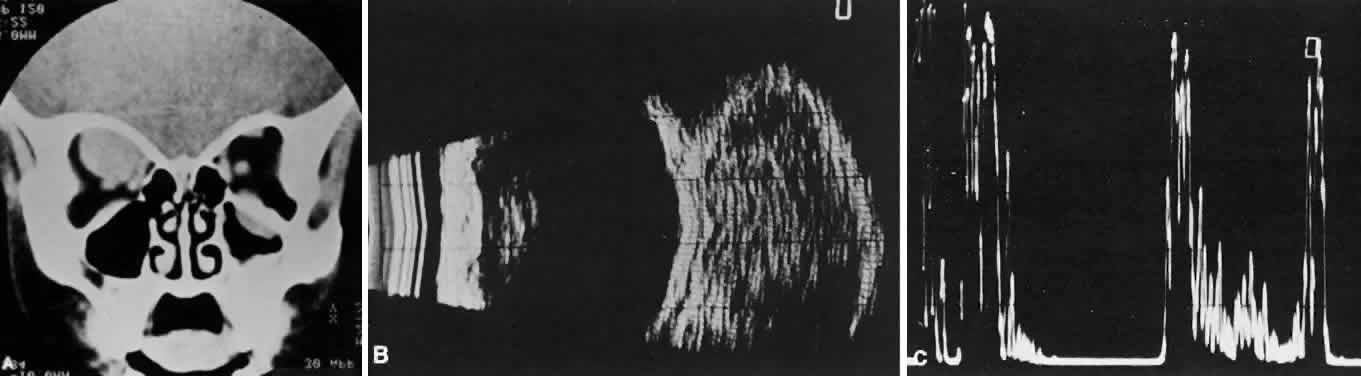

of the globe. CT scans show the topography of the orbital mass (Fig. 1A), as well as the possible extension into adjacent bone, paranasal sinuses, or

infiltrates normal tissue. Echography shows internal echoes of

low-to-medium amplitude. Because the cellular tumor absorbs acoustic

energy, the amplitude of the spikes falls off somewhat through the lesion (see Fig. 1B and C). MRI can help define the tumor's relationship to extraocular muscles (Fig. 2).  Fig. 1. A. Proptosis and downward, outward globe displacement developed over 2 days

in a 3-year-old girl. A homogeneous mass fills the superomedial orbit. B. Contact B-scanning shows a relatively well-circumscribed mass with uniform

internal echoes. C. Contact A-scanning shows the internal reflectivity to be of low to medium

amplitude, consistent with a sarcomatous lesion. Biopsy results confirmed

the diagnosis of rhabdomyosarcoma. Fig. 1. A. Proptosis and downward, outward globe displacement developed over 2 days

in a 3-year-old girl. A homogeneous mass fills the superomedial orbit. B. Contact B-scanning shows a relatively well-circumscribed mass with uniform

internal echoes. C. Contact A-scanning shows the internal reflectivity to be of low to medium

amplitude, consistent with a sarcomatous lesion. Biopsy results confirmed

the diagnosis of rhabdomyosarcoma.

Fig. 2. MRI shows an intraconal tumor of lower intensity than the medial rectus

muscle. The proximal muscle is splayed rather than compressed, suggesting

that the lesion originated within the medial rectus. The diagnosis

was alveolar rhabdomyosarcoma. Fig. 2. MRI shows an intraconal tumor of lower intensity than the medial rectus

muscle. The proximal muscle is splayed rather than compressed, suggesting

that the lesion originated within the medial rectus. The diagnosis

was alveolar rhabdomyosarcoma.